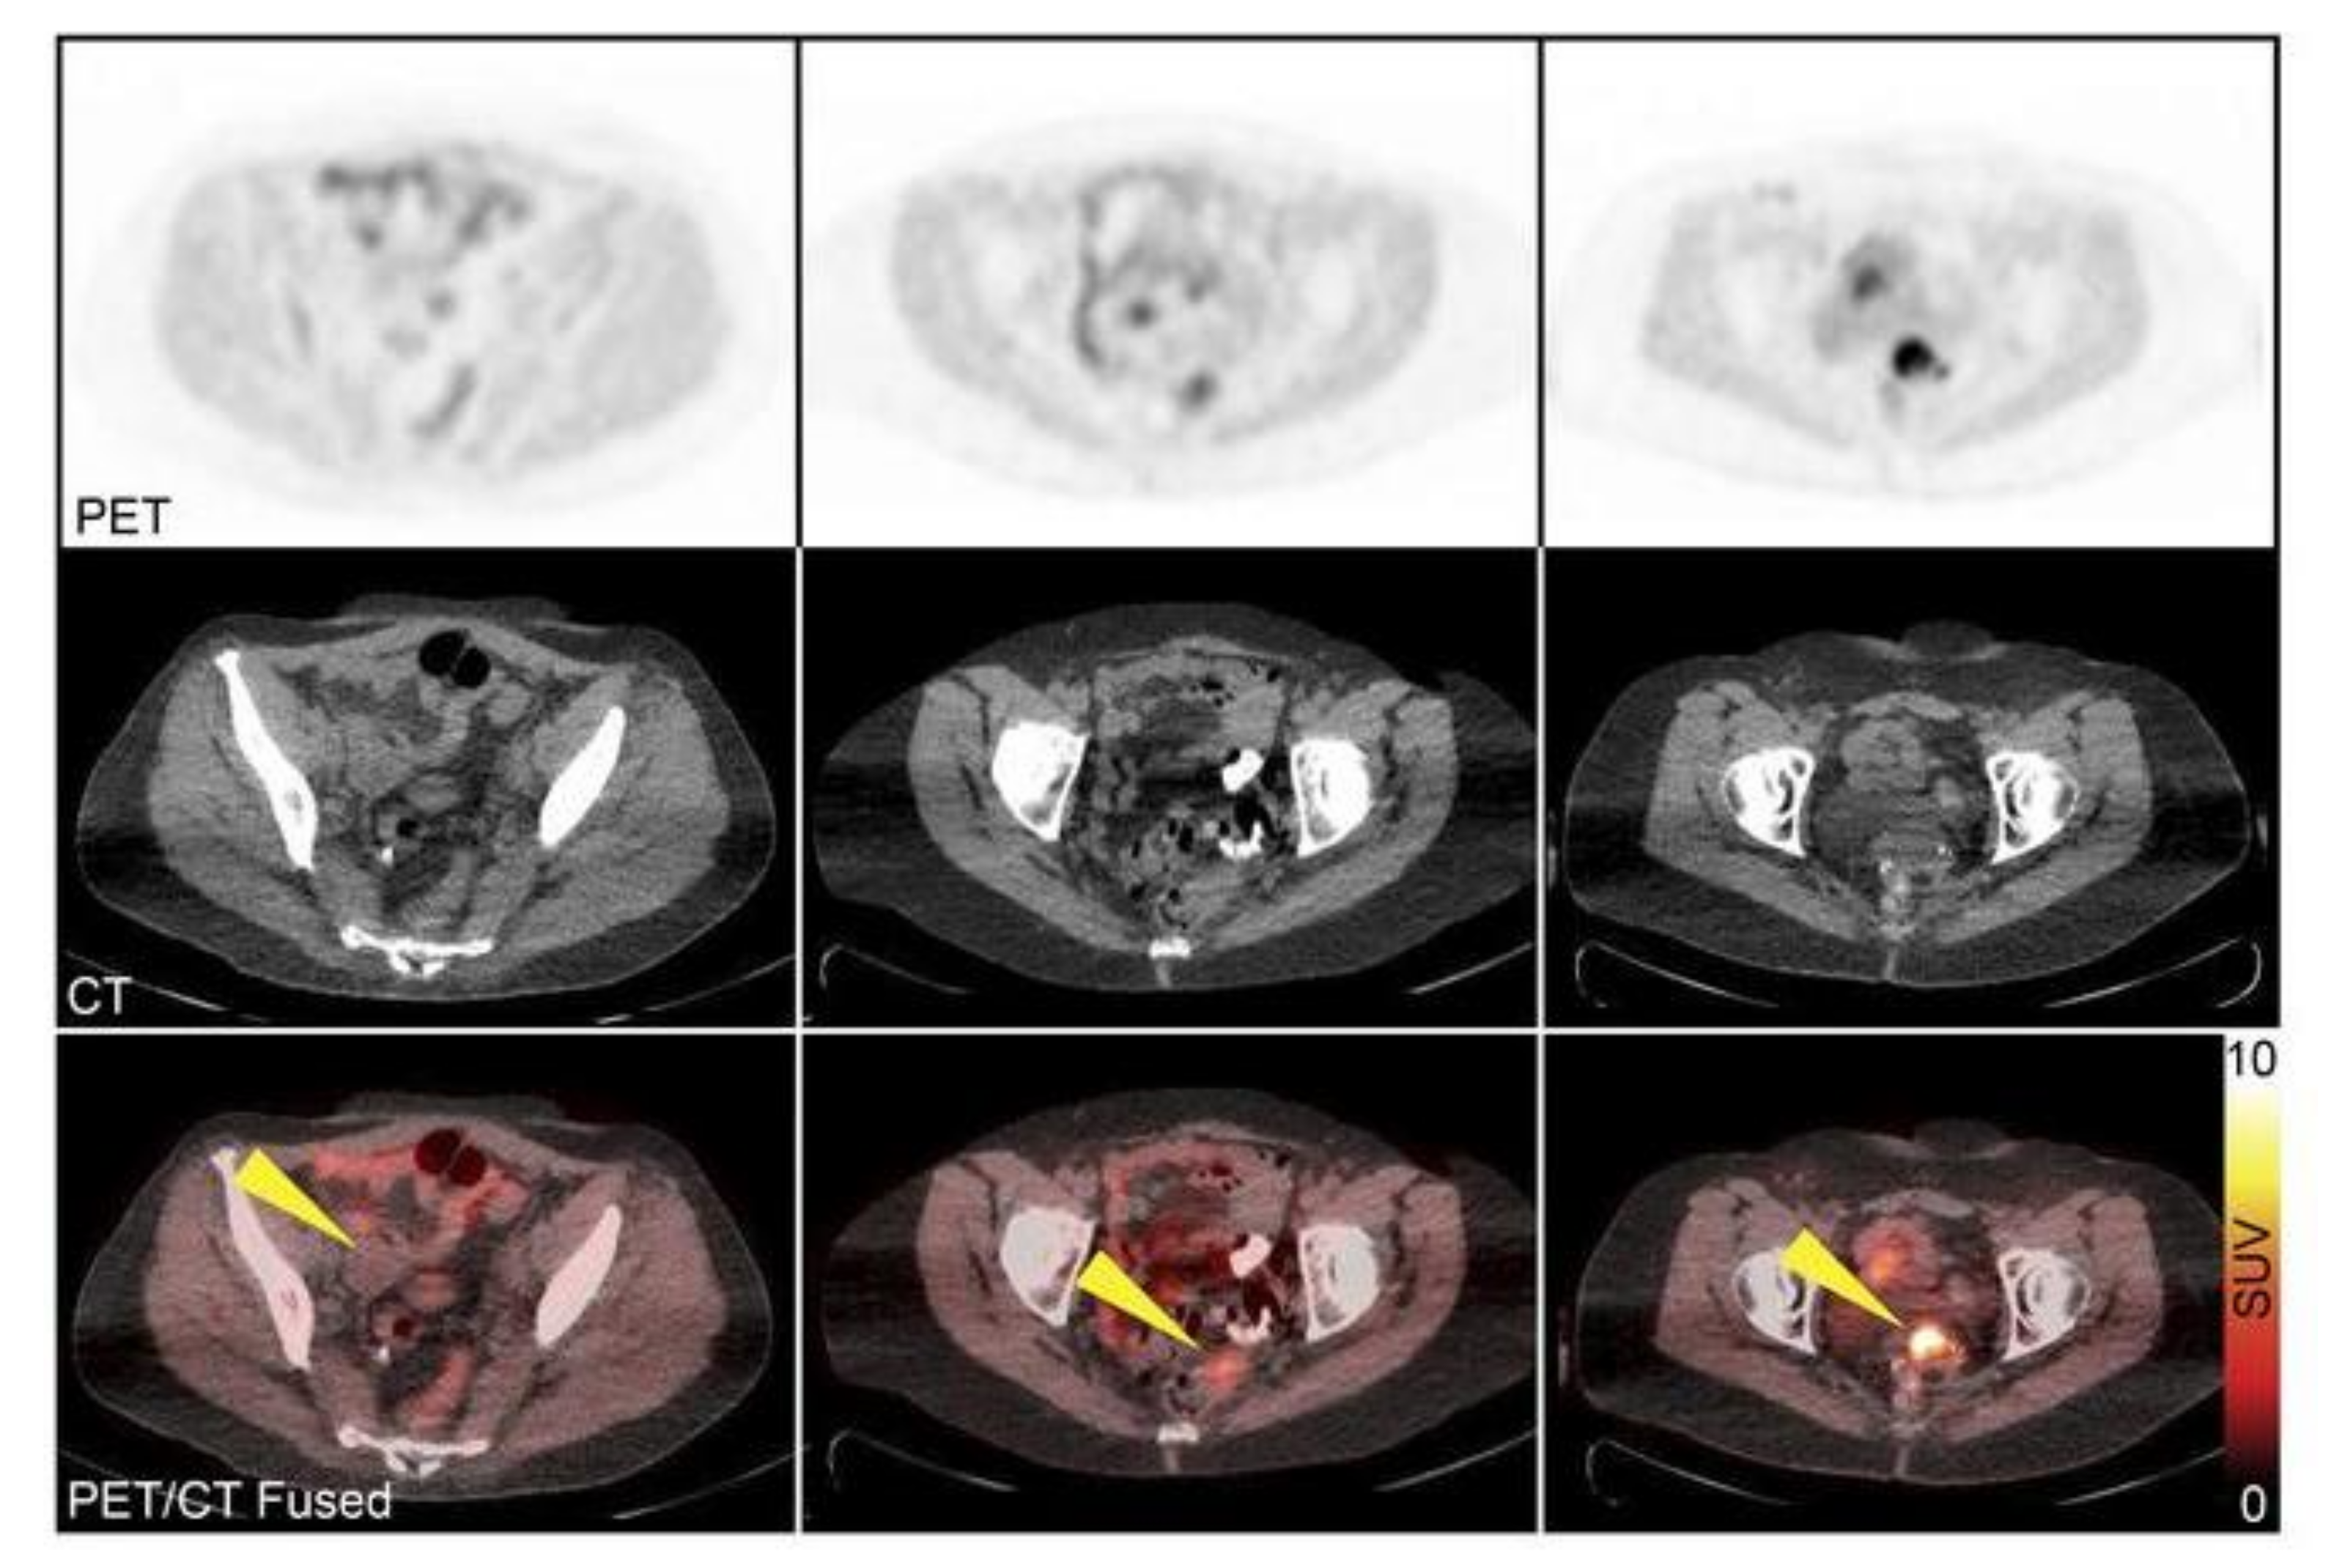

- Makvandi, M.; Pantel, A.; Schwartz, L.; Schubert, E.; Xu, K.; Hsieh, C.-J.J.; Hou, C.; Kim, H.; Weng, C.-C.C.; Winters, H.; et al. A PET imaging agent for evaluating PARP-1 expression in ovarian cancer. J. Clin. Invest. 2018, 128, 2116–2126. [Google Scholar] [CrossRef]